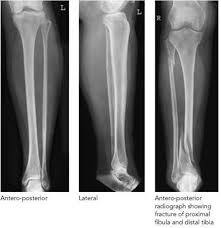

Medifyhome provides comprehensive X-Ray Both Lower Limb imaging to capture clear, front-to-back views of both legs, including the femur, tibia, fibula, knees, ankles, and feet. This scan is vital for diagnosing fractures, bone deformities, joint issues, infections, and other abnormalities affecting the lower limbs. Conducted at NABL and NABH-certified diagnostic centers, our imaging services offer precise and trustworthy results to aid effective treatment planning. With a focus on quality and affordability, Medifyhome is your reliable partner for expert diagnostic solutions.